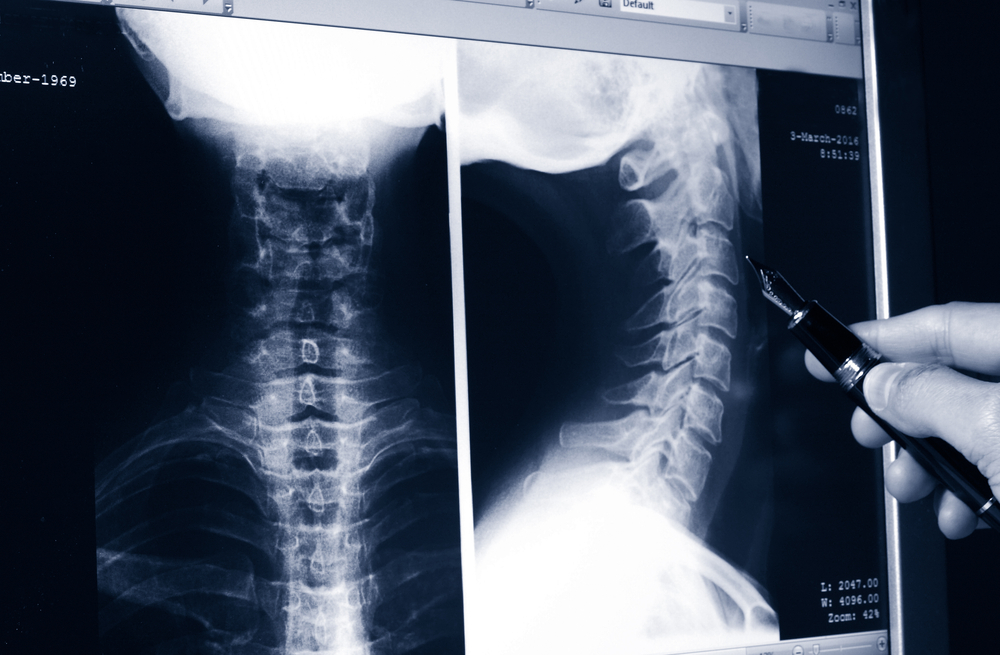

Рентгенография органов шеи может выполняться в прямой или боковой проекции. Нередко ее назначают прицельно для осмотра гортани или глотки.

- На снимках в боковой проекции четко визуализируется просвет гортани в виде изогнутой полосы просветления, являющийся продолжением глотки и переходящий в трахею.

- Также видны хрящи гортани (надгортанный, перстневидный и щитовидный), подъязычная кость, надгортанник, желудочки гортани.

- На рентгенограммах в прямой проекции можно различить щитовидный хрящ, подголосовое пространство и иногда верхний и средний отделы гортани.